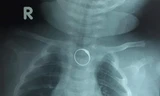

Xét nghiệm máu, bệnh nhân có tình trạng thiếu máu nặng, suy gan cấp, tổn thương thận cấp, rối loạn nước-điện giải và rối loạn toan-kiềm. Bệnh nhân nhanh chóng được cấp cứu ban đầu, sau đó được điều trị chuyên sâu bằng thuốc vận mạch để duy trì huyết áp; thở máy, lọc máu liên tục, lọc máu chu kỳ và thay huyết tương để hỗ trợ các tạng suy. Ngoài ra, bệnh nhân còn phải truyền một khối lượng lớn máu và các chế phẩm của máu. Hiện tại, bệnh nhân đã qua cơn nguy kịch nhưng vẫn đang phải điều trị và chăm sóc tích cực.

Bệnh nhân thứ hai là nam giới, 28 tuổi, đi ăn cỗ có món ăn được chế biến với lá du mại. Sau vài hôm, bệnh nhân xuất hiện mệt mỏi, vàng da, vàng mắt, đi tiểu ít và nước tiểu màu đỏ. Nhập viện trong tình tạng mệt nhiều, da xanh, niêm mạc-củng mạc mắt vàng. Xét nghiệm máu có tình trạng thiếu máu nặng, suy gan cấp, tổn thương thận cấp và rối loạn nước-điện giải. Bệnh nhân được điều trị tích cực, truyền máu nhiều lần. Hiện tại, bệnh nhân đã qua cơn nguy kịch và đang được theo dõi sát tình trạng sức khỏe.